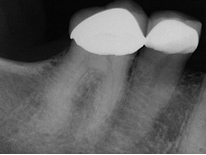

Conventional Treatment with Standard Core Restoration

Non-surgical endodontic treatment with resin core build up

All Treatment performed by Dr. Brian A. Christopherson